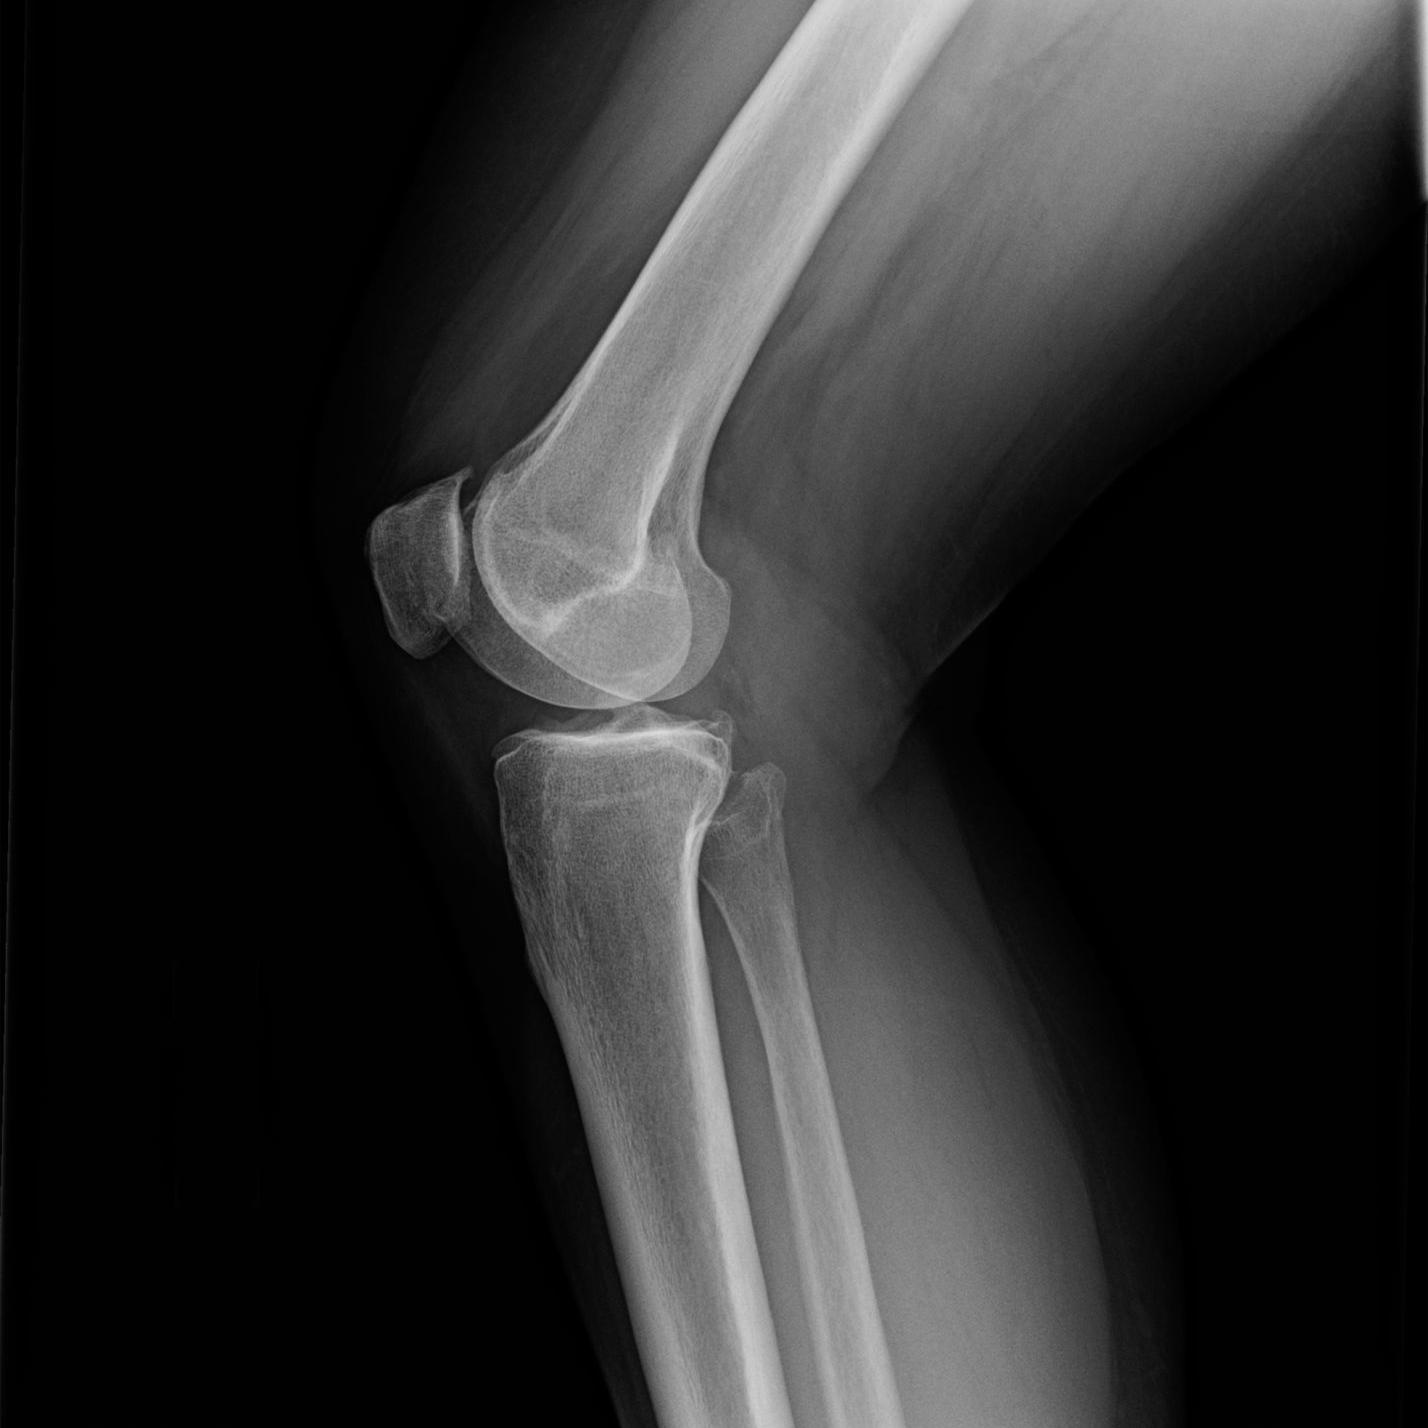

2132021 Knee bone spurs also known as osteophytes may occur at the end of the thigh bone shin bone or knee cap in areas where the cartilage has worn away.

There is no treatment required for stage 0 osteoarthritis. Bone spurs within the knee can cause pain and limit joint mobility which can cause difficulty with everyday activities like walking squatting bending and going up and down stairs and can lead to muscle imbalances in the leg. Bone spurs osteophytes in the knee are small bony outgrowths caused by excessive friction between the surfaces of the joint.

11202019 A bone spur osteophyte is a tiny pointed outgrowth of bone. In this stage patients may develop very minor wear and tear and bone spur growths at the end of the knee joints. 4102018 These bony growths or bone spurs on the knee are smooth as opposed to jagged.